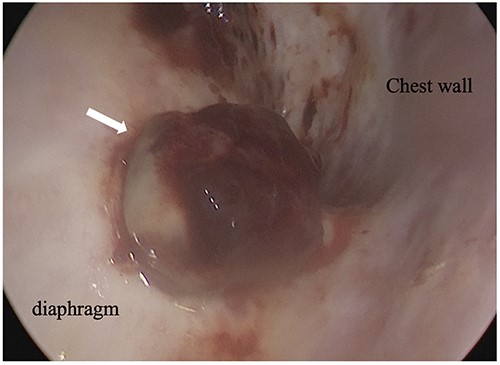

An 81-year-old man who underwent surgical resection for lung cancer 2 years previously was referred for the examination of a right diaphragmatic mass that was pointed out during follow-up. Computed tomography (CT) revealed pleural effusion and two contrast-enhanced nodules (17 × 10 and 10 × 10 mm) in the right diaphragm (Fig. 1A); however, he had no symptoms. Positron emission tomography (PET)/CT was performed, but no FDG accumulation was found (Fig. 1B). Although hemangioma was suspected based on the preoperative imaging, we were unable to exclude the recurrence of lung cancer. Therefore, the patient was admitted for the examination of the right diaphragmatic nodules by VATS. A 4-cm thoracotomy wound was created at the 8th intercostal mid-axillary line, and a 5.5-mm port was created at the 6th intercostal anterior axillary line. Observation of the thoracic cavity revealed reddish brown pleural effusion and two large and small pedunculated tumors on the diaphragm (Fig. 2). The smaller nodule spontaneously fell off during the process of cleaning the thoracic cavity and was submitted for a rapid intraoperative diagnosis. As hemangiomas were diagnosed during the operation, the roots of the smaller nodule and the larger nodule that fell off were treated using an ultrasonic coagulation and incision device while partially leaving the abdominal layer of the diaphragm. Partial excision was performed (Fig. 3). The nodules were 1.7 × 1.7 and 1.5 × 1.5 cm with a brown surface (Fig. 4). Histopathologically, the nodules were mostly blood clots, and a collection of thin-walled blood vessels with red blood cells was observed (Fig. 5A). An immunohistochemical analysis revealed that the vascular endothelial cells were positive for CD31 and CD34 (Fig. 5B). Thus, the nodules were diagnosed as diaphragmatic hemangioma. No hemangiomatous lesions were noted in the normal connective tissue in the additional resected tissue specimens (Fig. 6). The postoperative course was normal, and the patient is being followed up in an outpatient setting. It has been 16 months since the operation, but no recurrence has been observed at this time.

Intraoperative thoracoscopic image, and two consecutive reddish, smooth nodules were observed on the surface of the diaphragm.

Intraoperative thoracoscopic image, and the diaphragm layer was peeled off with the active blade of the ultrasonic coagulation and incision device.

In partial resection in the clinical setting, the use of an electric scalpel is difficult because electrical stimulation stimulates the movement of the diaphragm. Therefore, in this case, the operation was performed using the active blade of the ultrasonic coagulation and incision device, and the root excision operation was completed.